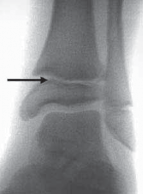

Chapter 18 Operative Management of Pediatric Ankle Fractures Bryan T. Leek and Scott J. Mubarak DEFINITION An…